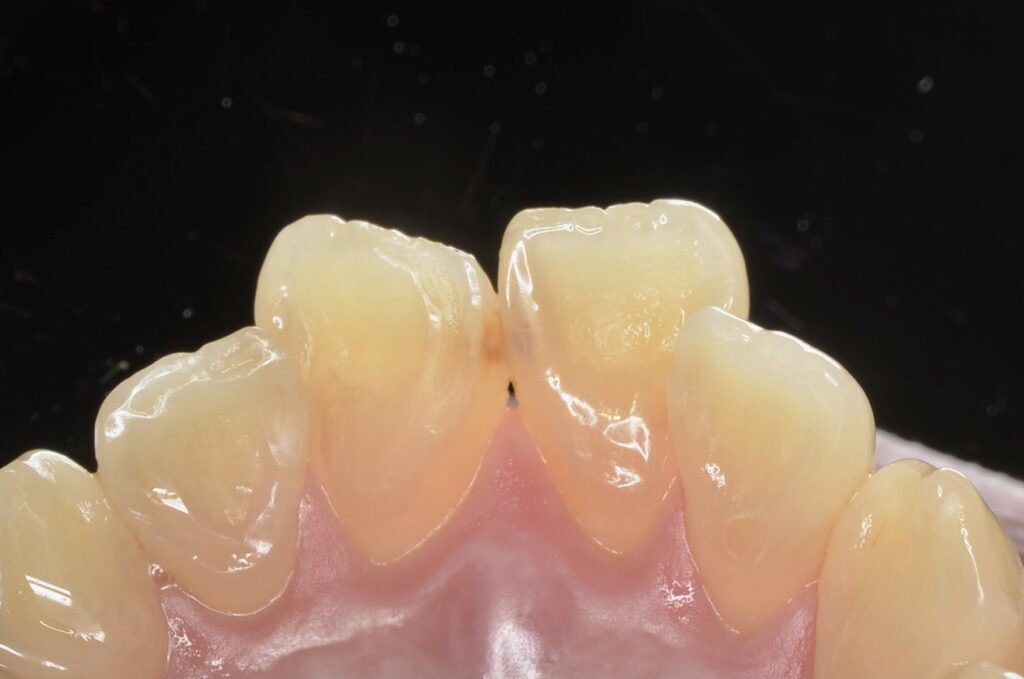

20代 虫歯治療 ダイレクトボンディング #50

Before

After

| 年齢 | 20代 | 治療方法 | ダイレクトボンディング |

|---|---|---|---|

| 性別 | 女性 | 通院回数 | 2回 |

| 主訴 | 歯が痛い | 費用 | 60,500円(税込) |

| 治療のメリット | 歯を削る量を少なくできる・自然な見た目・境目がピッタリできる | ||

| 治療のデメリット | 大きい虫歯治療には適応できない場合がある | ||